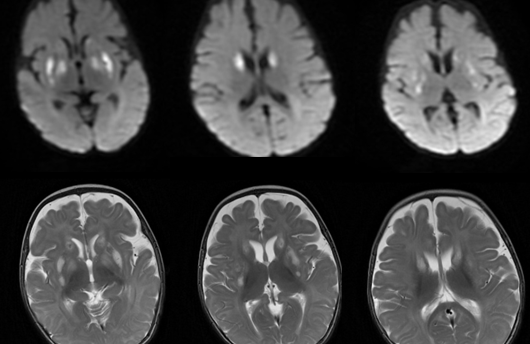

1.1951年英國神經(jīng)病理學家Leigh首報。2.發(fā)病率1/40000。≤10歲發(fā)病。≤2歲內(nèi)多見。通常兒童期死亡。成人型偶見。3.丙酮酸脫氫酶復合物(PDHC)和細胞色素C氧化酶(COX)遺傳缺陷。75%為核線粒體(nDNA)突變,以孟德爾方式遺傳。為AE遺傳和X-link遺傳。25%為線粒體DNA(mtDNA)突變,通過母親遺傳。4.臨床表現(xiàn)包括:精神運動遲緩/退化.共濟失調(diào)肌張力障礙眼肌麻痹癲癇乳酸酸中毒呼吸節(jié)律紊亂基底神經(jīng)節(jié)和腦干功能障礙5.標志物為CSF乳酸增高。MRS急性期Lac峰非特異性增高,Cho峰增高,NAA峰降低。MR:長T1(可見部分短T1和增強)長T2/FLAIR。DWI時間分布上呈多樣性,急性期可見彌散受限。表現(xiàn)為三型:1)基底型:雙側(cè)對稱殼核受累為必備特征。其它區(qū)域不同程度受累。2)腦干型3)白質(zhì)型